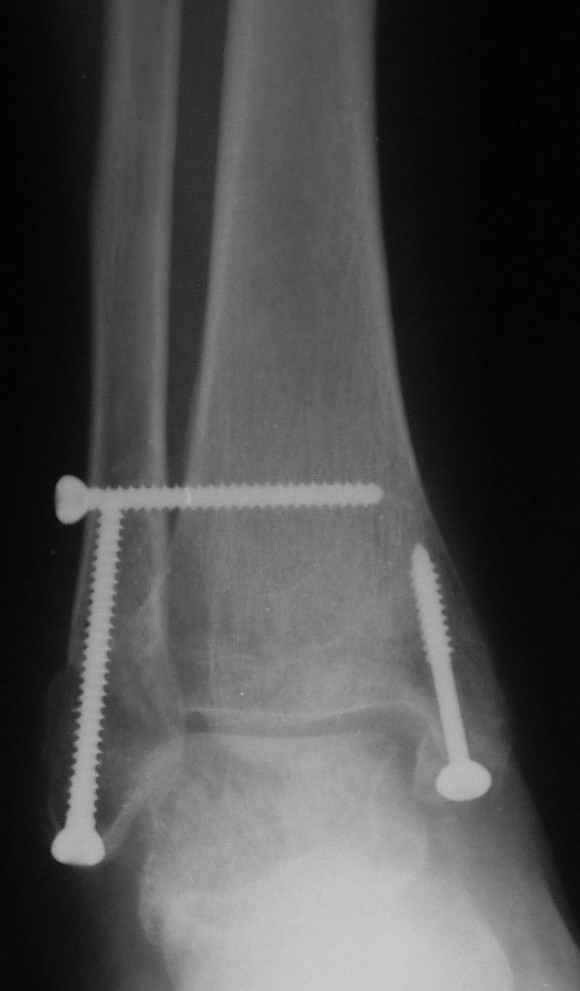

Через месяц

Боковой через месяц

Риторический вопрос - в каком руководстве рекомендован такой способ остеосинтеза наружной лодыжки?

Очевидно, такой результат операции был запрограммирован. При невосстановленной длине и практически нефиксированной малоберцовой кости (этот кортикальный винт - как карандаш в стакане), при неустраненном подвывихе, невправленной и тоже нефиксированной внутренней лодыжке нет стабильной вилки сустава. Если такую операцию сделать даже сразу, а не через 4 месяца, то результат ожидаем

тот же.

Вариант с артродезом уже обсудили. Хотя, после увиденых снимков, пессимизм насчет восстановительной операции у меня, например, несколько уменьшился. Особенного уж какого-то остеопороза не видно даже на январских снимках. Можно черед мини-доступы убрать винты, аппаратом вправить малоберцовую кость, устранить подвывих стопы. Ну а дальше фиксировать малоберцовую пластиной сзади. А может, и напряженной Y-спицей попробовать - Анатолий Федорович, как Вы полагаете? Внутреннюю - то, что осталось, если уже не получится сделать спицами и проволокой, то что-то типа пластики дельтовидной связки. А может, и не трогать ее вовсе... В общем, выбор непростой,

много факторов надо взвесить.